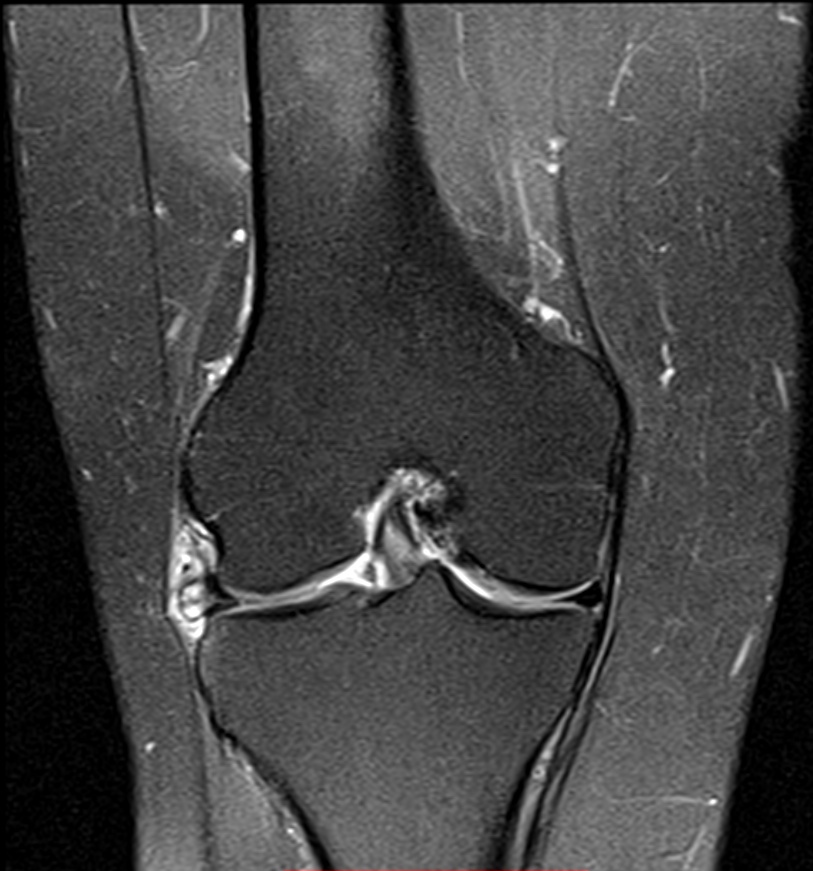

Lesão horizontal do menisco lateral e cisto parameniscal.

Corredora com dores na região do compartimento lateral do joelho e sensação de aumento de volume com formação de um nódulo palpável.

Realizado exame de ressonância magnética com identificação de lesão horizontal do menisco lateral (seta pequena) e formação cística parameniscal.